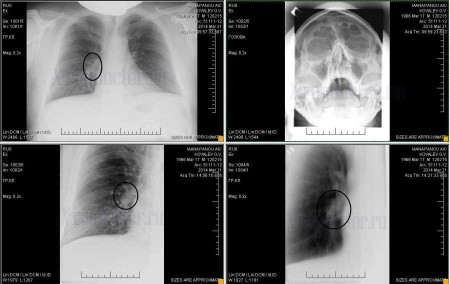

На представленной рентгенограмме в правой боковой проекции визуализируется тень до 5 см в диаметре с ровным четким контуром округлой формы. Передний и задний реберно-диафрагмальные синусы без особенностей. Контуры диафрагмы ровные, четкие.

На рентгеновском снимке увеличенный лимфоузел может проявиться в виде увеличенной тени, изменения контуров или увеличения плотности ткани в определенной области.